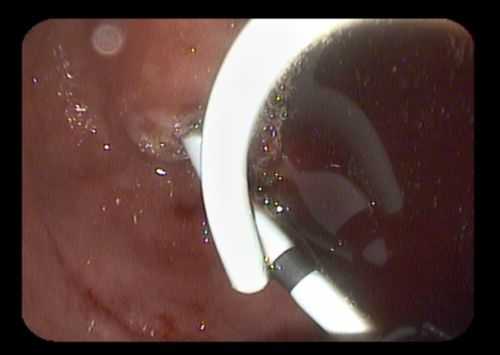

Затем под контролем рентгеноскопии в полость кисты вводится струна-проводник для установки пластикового стента (double pigtail) диаметром 10 Fr и длиной 10 см. Осуществляется рентгенологический и ультразвуковой контроль: он подтвердил, что дистальный конец стента располагается в просвете кисты, проксимальный - в луковице двенадцатиперстной кишки (рис. 5 в, рис. 6). При эндоскопическом осмотре оценивается область сформированного соустья для исключения кровотечения (рис. 7).

В 7 случаях пациентам с постнекротическими кистами, содержащими секвестры, выполнено эндоскопическое цистогастральное стентирование с использованием металлического покрытого саморасширяющегося стента диаметром 10 мм (рис. 2, 3), с временной установкой санационного цистоназального катетера через просвет стента.

Рис. 2. Фотография при эндоскопии. В просвете желудка визуализируется саморасширяющийся покрытый металлический стент и установленный через его просвет цистоназальный дренаж